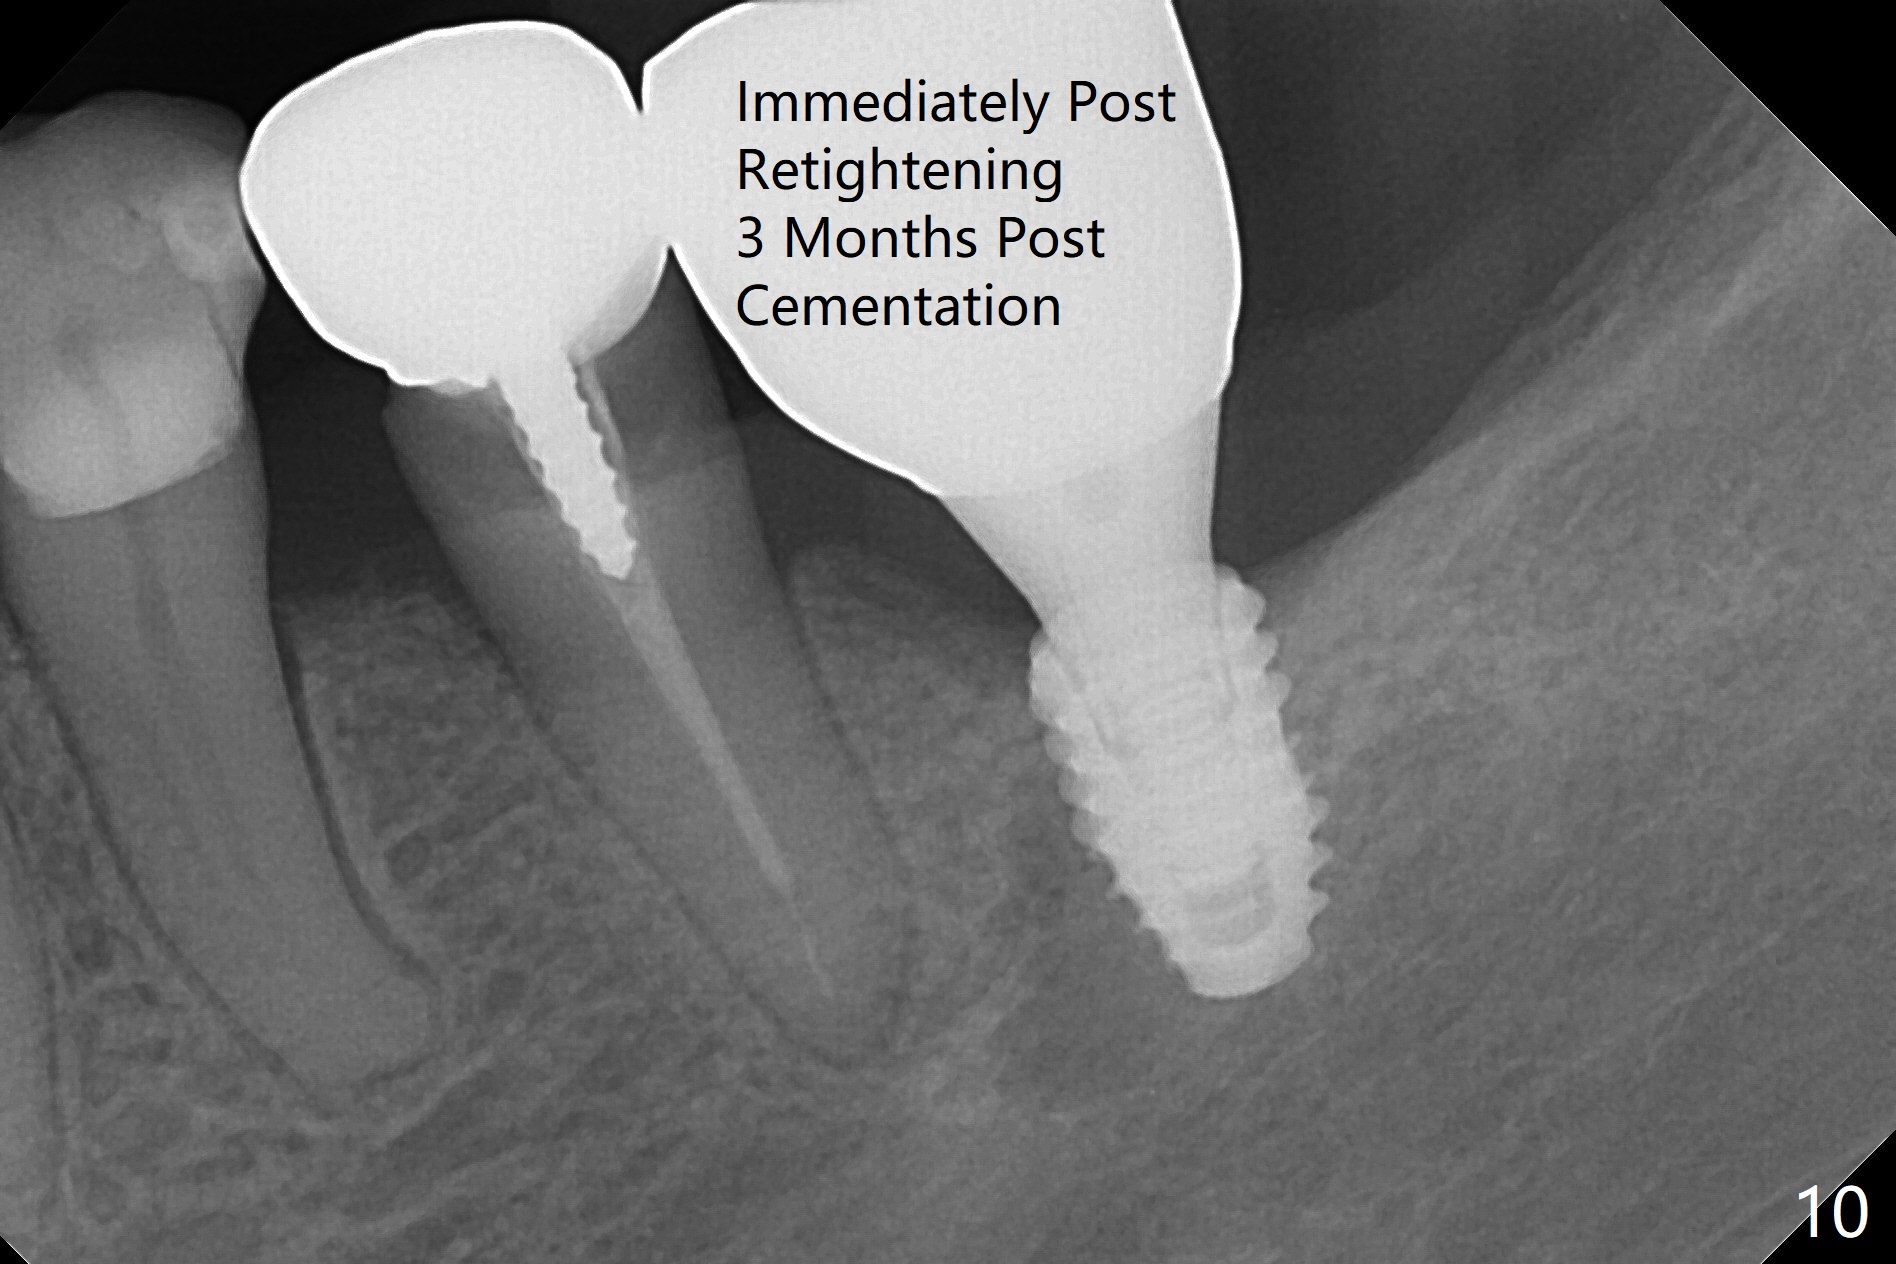

M

As a surgeon, I have never felt that my scalpel is as precise as media claims to be until guided surgery is introduced. The implants at #14 and 19 are placed as precisely as planned as well as painlessly and quickly (Fig.1-4). What else can we ask for? The gingiva around the healing abutment (5.5x3 mm) at #19 is erythematous (Fig.5). Later a longer healing abutment is used (Fig.6 (5.5x5 mm)). There is no bone loss 5 months or 7 months postop (Fig.6-9). The abutment screw is loose 3 months post cementation due to unfavorable crown/implant ratio (Fig.10); in fact the abutment is incompletely seated. Bicon implants will be in consideration to reduce screw loosening if implants are to be placed at #15 and 18. The abutment screw at #14 becomes loose 10 months post cementation; after retorque at #30 Ncm, the abutment is incompletely seated (Fig.11). It remains the same after use of 4.6 and 5.6 mm profile drills (Fig.12). A healing abutment is placed. When the patient returns, use planning kit and try to place a 5.2x5.5(2) cemented abutment. In fact it works (Fig.13). The crown at #19 is loose again 1 year 5 months post retightening. After removing crown/abutment, the mesial surface of the crown is heavily reduced. The crown/abutment is reseated to make sure that there is no proximal contact between the neighboring teeth (Fig.14 arrow). Because of tilt of the PA, it is difficult to tell the tightness of the contact between the implant and abutment, but the apical space is significantly reduced (*, as compared to Fig.10). Pick up impression is taken for porcelain addition occlusomesially. Two months later the patient returns for crown recementation. When the abutment is reseated with the repaired crown, the seating is incomplete (Fig.15). The abutment is completely seated when it is turned free hand with the flat surface of the abutment faces distal (Fig.16 D). The screw is torqued 20 Ncm before reimpression.